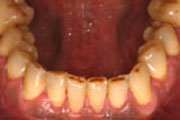

paradobtalno zdravljenje Pred parodontalnim zdravljenjem

paradontalno zdravljenje 2 Po zaključku parodontalnega zdravljenja